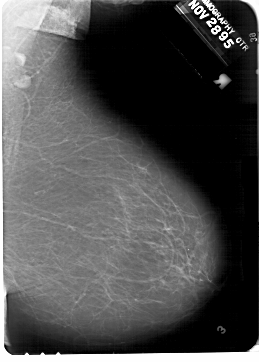

A_1332_1.RIGHT_MLO

RIGHT_MLO LINES 6871 PIXELS_PER_LINE 4906 BITS_PER_PIXEL 12 RESOLUTION 43.5 NON_OVERLAY